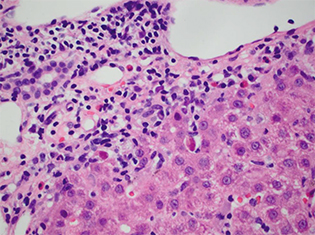

A hepatologist wanted to know if a jaundiced patient was still imbibing alcohol. The patient had a history of past alcohol abuse and was transplanted for alcoholic steatohepatitis. In an image he showed of the biopsy of the woman’s transplanted liver (Fig. 1), Dr. Najarian noted there was clearly an active steatohepatitis present. But then he described a feature visible in the center of the image: “This very large sort of smudgy-looking cell with some eosinophilic—what look like—inclusions.”

The biopsy really had two stories to tell, Dr. Najarian said. One was alcohol use. The patient had not been following up with her physicians but returned for care after her skin became yellow after heavy drinking at home. And she had cytomegalovirus infection, commonly seen in post-transplant patients.